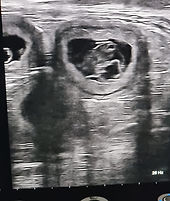

Lisa_Havaneser_2024-08-21_09-30-11_Abdomen_LL.jpg